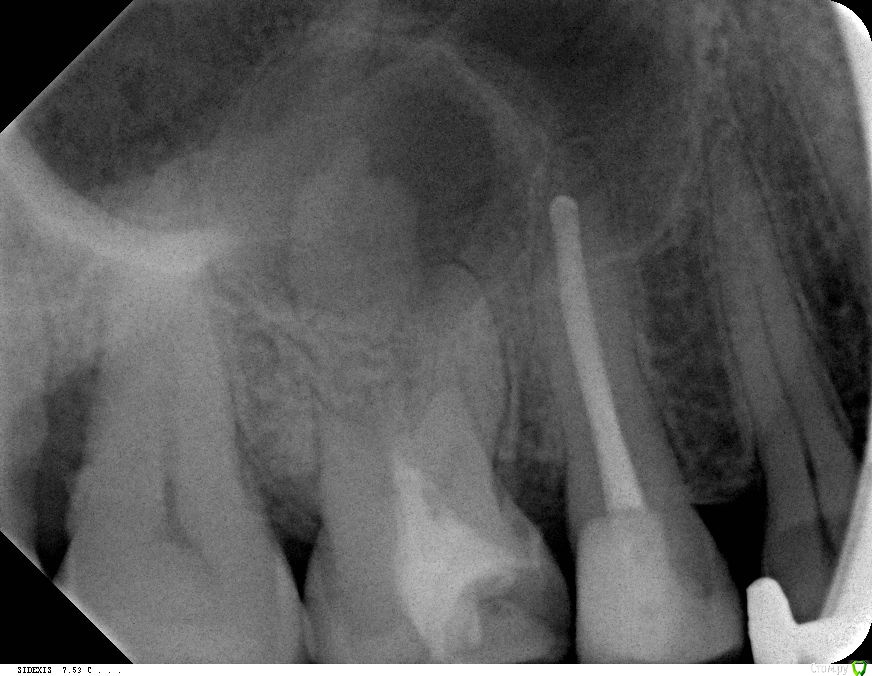

SDC Опубликовано 18 февраля, 2015 Поделиться Опубликовано 18 февраля, 2015 так оно и есть: первый врач - удалять, второй (клиника университетская) - резекция, этого нашел через коллег. Он похоже знает что надо делать, но до сих пор не имел дела с "русской" спецификой.Искать бывшего соотечественника сложно - городишко наш небольшой. Передайте, что если санкции продолжатся, то скоро все "русские зубы" будут такими и держите наготове телефон с открытым инстаграмм - немецкие одонтологи с ума сойдут.А где лечили 15 зуб и 36?На дистальном корне 36 тоже проблемка есть. Вы немецким коллегам подскажите, что небный (палатинальный) канал прямой и пройти его на 1/2 может студент в России.В области верхушек вестибулярных/щечных корней вроде бы нет воспаления в периодонте.Немец из университесткой не может пройти прямой канал, но рекомендует апико небного корня? (это можно сделать только со стороны неба и очень сложно) Ну и в конце концов, не так дорого и в Россию смотаться, особенно, если платят в евро, а все авиакомпании сильно просели в отношении стоимости перелетов. Ссылка на комментарий

DmitrySH Опубликовано 18 февраля, 2015 Поделиться Опубликовано 18 февраля, 2015 На щечных тоже есть, но существенно меньше Ссылка на комментарий

SDC Опубликовано 18 февраля, 2015 Поделиться Опубликовано 18 февраля, 2015 (изменено) На щечных тоже есть, но существенно меньшеА где? Я практически везде вижу периодонтальную щель, зато на небном резорбцию и приличную деструкцию кости. Изменено 18 февраля, 2015 пользователем SDC Ссылка на комментарий

DmitrySH Опубликовано 18 февраля, 2015 Поделиться Опубликовано 18 февраля, 2015 ...офф топ, что-то в этом браузере цитировать не могу вдруг.. не пойму. Вокруг щечных корней такие небольшие "пузыри". На дистальном чуть больше, примерно 1-1.5 мм вокруг апекса Ссылка на комментарий

SDC Опубликовано 18 февраля, 2015 Поделиться Опубликовано 18 февраля, 2015 ...офф топ, что-то в этом браузере цитировать не могу вдруг.. не пойму. Вокруг щечных корней такие небольшие "пузыри". На дистальном чуть больше, примерно 1-1.5 мм вокруг апексаВ общем, КТ надо смотреть - диагностика будет точнее Ссылка на комментарий